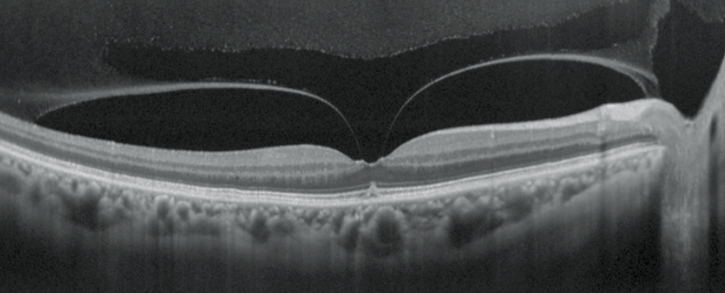

視網膜分析

高清追蹤plus功能

高清追蹤plus功能可追蹤無意識的眼球運動,在SLO圖像上保持相同的掃描位置,確保精確的圖像采集。此功能可獲得多至120張疊加的高清圖像。